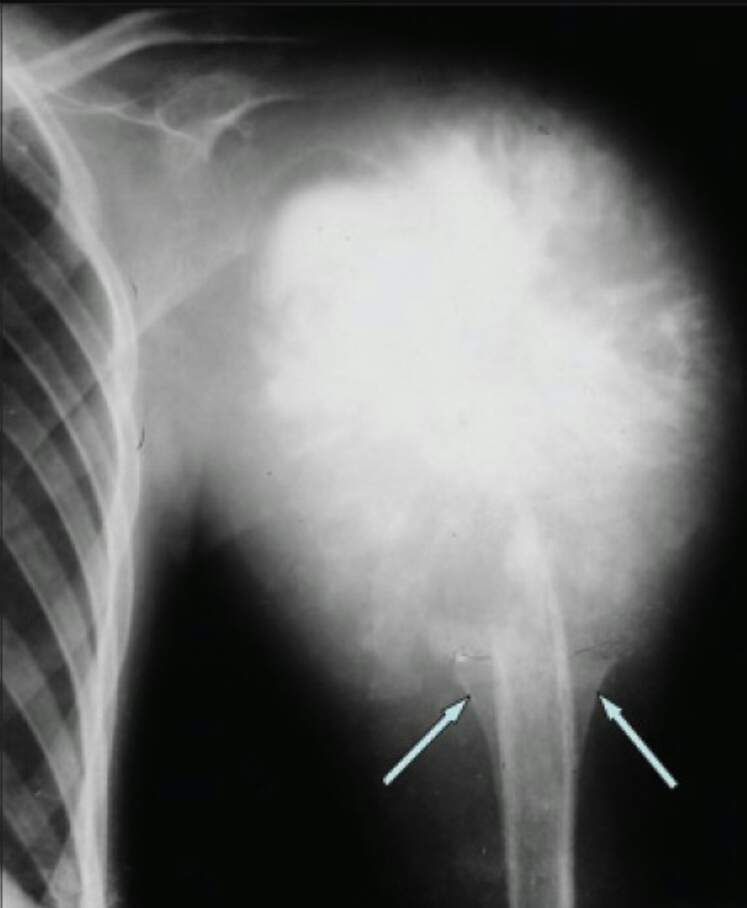

Findings? Diagnosis?

Sunburst periosteal reaction, dense sclerotic lesion at the proximal aspect of the humerus in the metaphyseal region, Codman triangle

Osteosarcoma